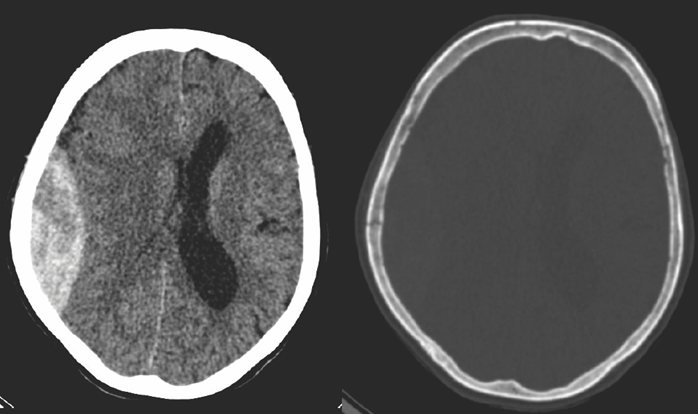

• Rupture of the meningeal arteries may give rise to an epidural hematoma. At the site of the hematoma skull fracture can be observed.

4.Middle-aged man some days after direct head trauma. On noncontrast CT a lens-shaped, slightly inhomogenous epidural hematoma can be seen, that causes compression of the right lateral ventricle (left panel). In bone window skull fracture without dislocation can be found at the site of the hematoma (right panel).